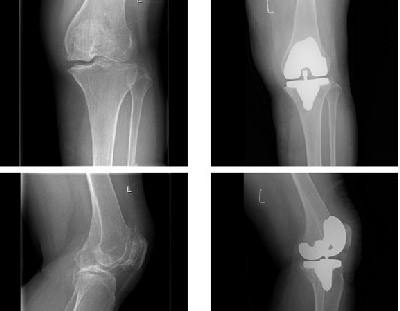

2、造成下山时膝盖痛的原因 这种膝盖痛的病状有些帖子上说叫是髌骨下滑囊炎,听说目前医学上还没有行之有效的治疗方法。是什么原因造成这种病状呢?大体上应该是以下三种情况造成的。一是长时间超负荷行走造成;二是过量负重造成;三是下山时不正确的姿势或奔路造成。还有就是本身就有些旧伤引起等原因。总的来说都是属于冲击性过大造成的劳损慢性伤,一旦发现一般都比较严重了。

3、膝盖伤的治疗 一般发现病状时很多人都会用一些喷剂、药酒、药膏等治疗,这些药品只能起到暂时缓和的作用。 物理治疗也只能是起到治标的作用,休息一段时间可能有一点效,但以后走狠了症状同样还会出现。 有一次偶然看到一个关于这方面的手术治疗的电视,介绍说很成功,但国外的治疗费用好像是要上万美元。 我个人用过十余种药物,感觉最有效的还是酸痛灵,其次是香港产的黄道益活络油。酸痛灵价格比较贵,在国内要买一百多元,两周基本上治愈了我的旧伤。活络油擦完感觉很舒服,但治疗效果也只能起到暂时的作用。 每种药物对每个人的疗效是不同的,酸痛灵我介绍过很多人用,有人用了说好,也有人用了说没什么作用。我觉得药物治疗不是目的,我们应该把重点放在预防上去。